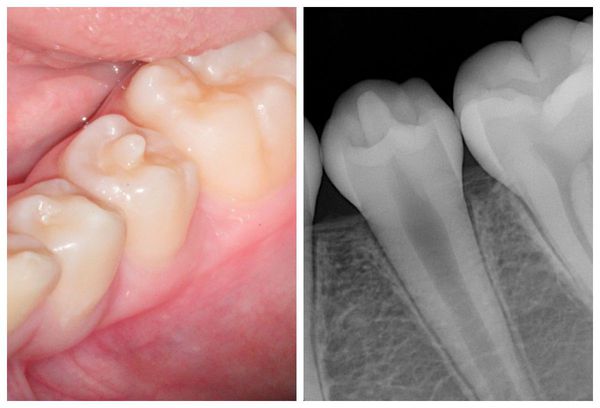

Podwojenie i zlanie zębów (fuzja lub germinacja) najczęściej prowadzą do problemów estetycznych — zęby wydają się zbyt duże, asymetryczne lub mają nieregularny kształt. Od typowego stłoczenia zębów (stłoczenie zębowe) można je odróżnić jedynie na podstawie badania rentgenowskiego, które pokazuje, czy zęby mają wspólne korzenie lub komory miazgi.

Przy taurodontyzmie (taurodontyzm) wygląd zewnętrzny zęba jest prawidłowy, ponieważ jego trzon i korzenie są przesunięte w głąb wyrostka zębodołowego (brzeg zębodołowy), co sprawia, że zmiana jest niewidoczna klinicznie. Anomalię tę można wykryć wyłącznie na zdjęciu rentgenowskim, gdzie widoczna jest powiększona komora miazgi i skrócone korzenie.

Zaburzenia takie jak zrośnięcie (fuzja) czy podwojenie zębów (geminacja) najczęściej dotyczą zębów przednich, szczególnie siekaczy, natomiast zrost korzeni (ankyloza, zrośnięcie) spotyka się głównie w obrębie drugich i trzecich trzonowców (molares) szczęki.

Do postawienia rozpoznania wystarczające jest badanie kliniczne uzupełnione zdjęciem rentgenowskim (radiogramem), które pozwala na ocenę liczby i kształtu korzeni oraz stopnia ewentualnego zlania tkanek.

Rozdwojony ząb (po lewej) i zrośnięte zęby (po prawej): wygląd zewnętrzny i zdjęcie rentgenowskie